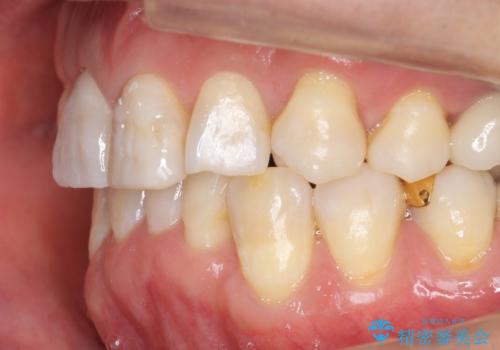

仕上がりに限界はありましたが、比較的短期間で歯並びが整いセラミック治療を行うことができ、患者様に「治療して良かった」とご満足頂けました。

左上1の歯の表面にもともと凹凸とグラデーションがあり、気になるようならセラミックでかぶせるのも一つだと提案しましたがご希望されなかったため、その表面性状を再現して右上1のセラミッククラウンを作製しています。

~被せ物の種類~

右上21:ジルコニアクラウン スペシャル

左上6:ジルコニアクラウン スタンダード

左上7:e-max press セラミックインレー